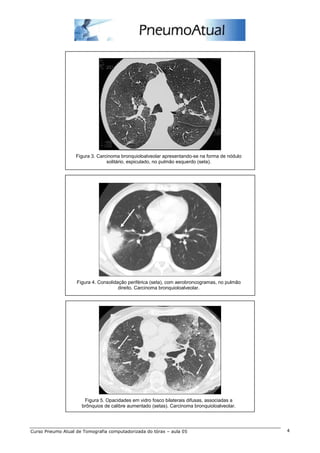

2.2 – Adenocarcinoma bronquioloalveolar

O carcinoma bronquioloalveolar (CBA) representa um subtipo de adenocarcinoma, responsável por 2% a

6% das neoplasias pulmonares. Tipicamente localiza-se na periferia brônquica, respeitando o interstício

pulmonar, o qual dá suporte para o crescimento tumoral. O CBA focal pode progredir para o envolvimento

pulmonar difuso, por meio de disseminação broncogênica. Na TC manifesta-se com diferentes aspectos,

dentre eles: nódulo solitário ou massa, em cerca de 43% dos casos (figura 3); consolidação, geralmente

com broncogramas aéreos, em 30% (figura 4); ou como anormalidade difusa caracterizada por nódulos ou

opacidades mal definidas, em cerca de 27% (figura 5).

Figura 3. Carcinoma bronquioloalveolar apresentando-se na forma de nódulo

solitário, espiculado, no pulmão esquerdo (seta).

Figura 4. Consolidação periférica (seta), com aerobroncogramas, no pulmão

direito. Carcinoma bronquioloalveolar.

Figura 5. Opacidades em vidro fosco bilaterais difusas, associadas a

brônquios de calibre aumentado (setas). Carcinoma bronquioloalveolar.